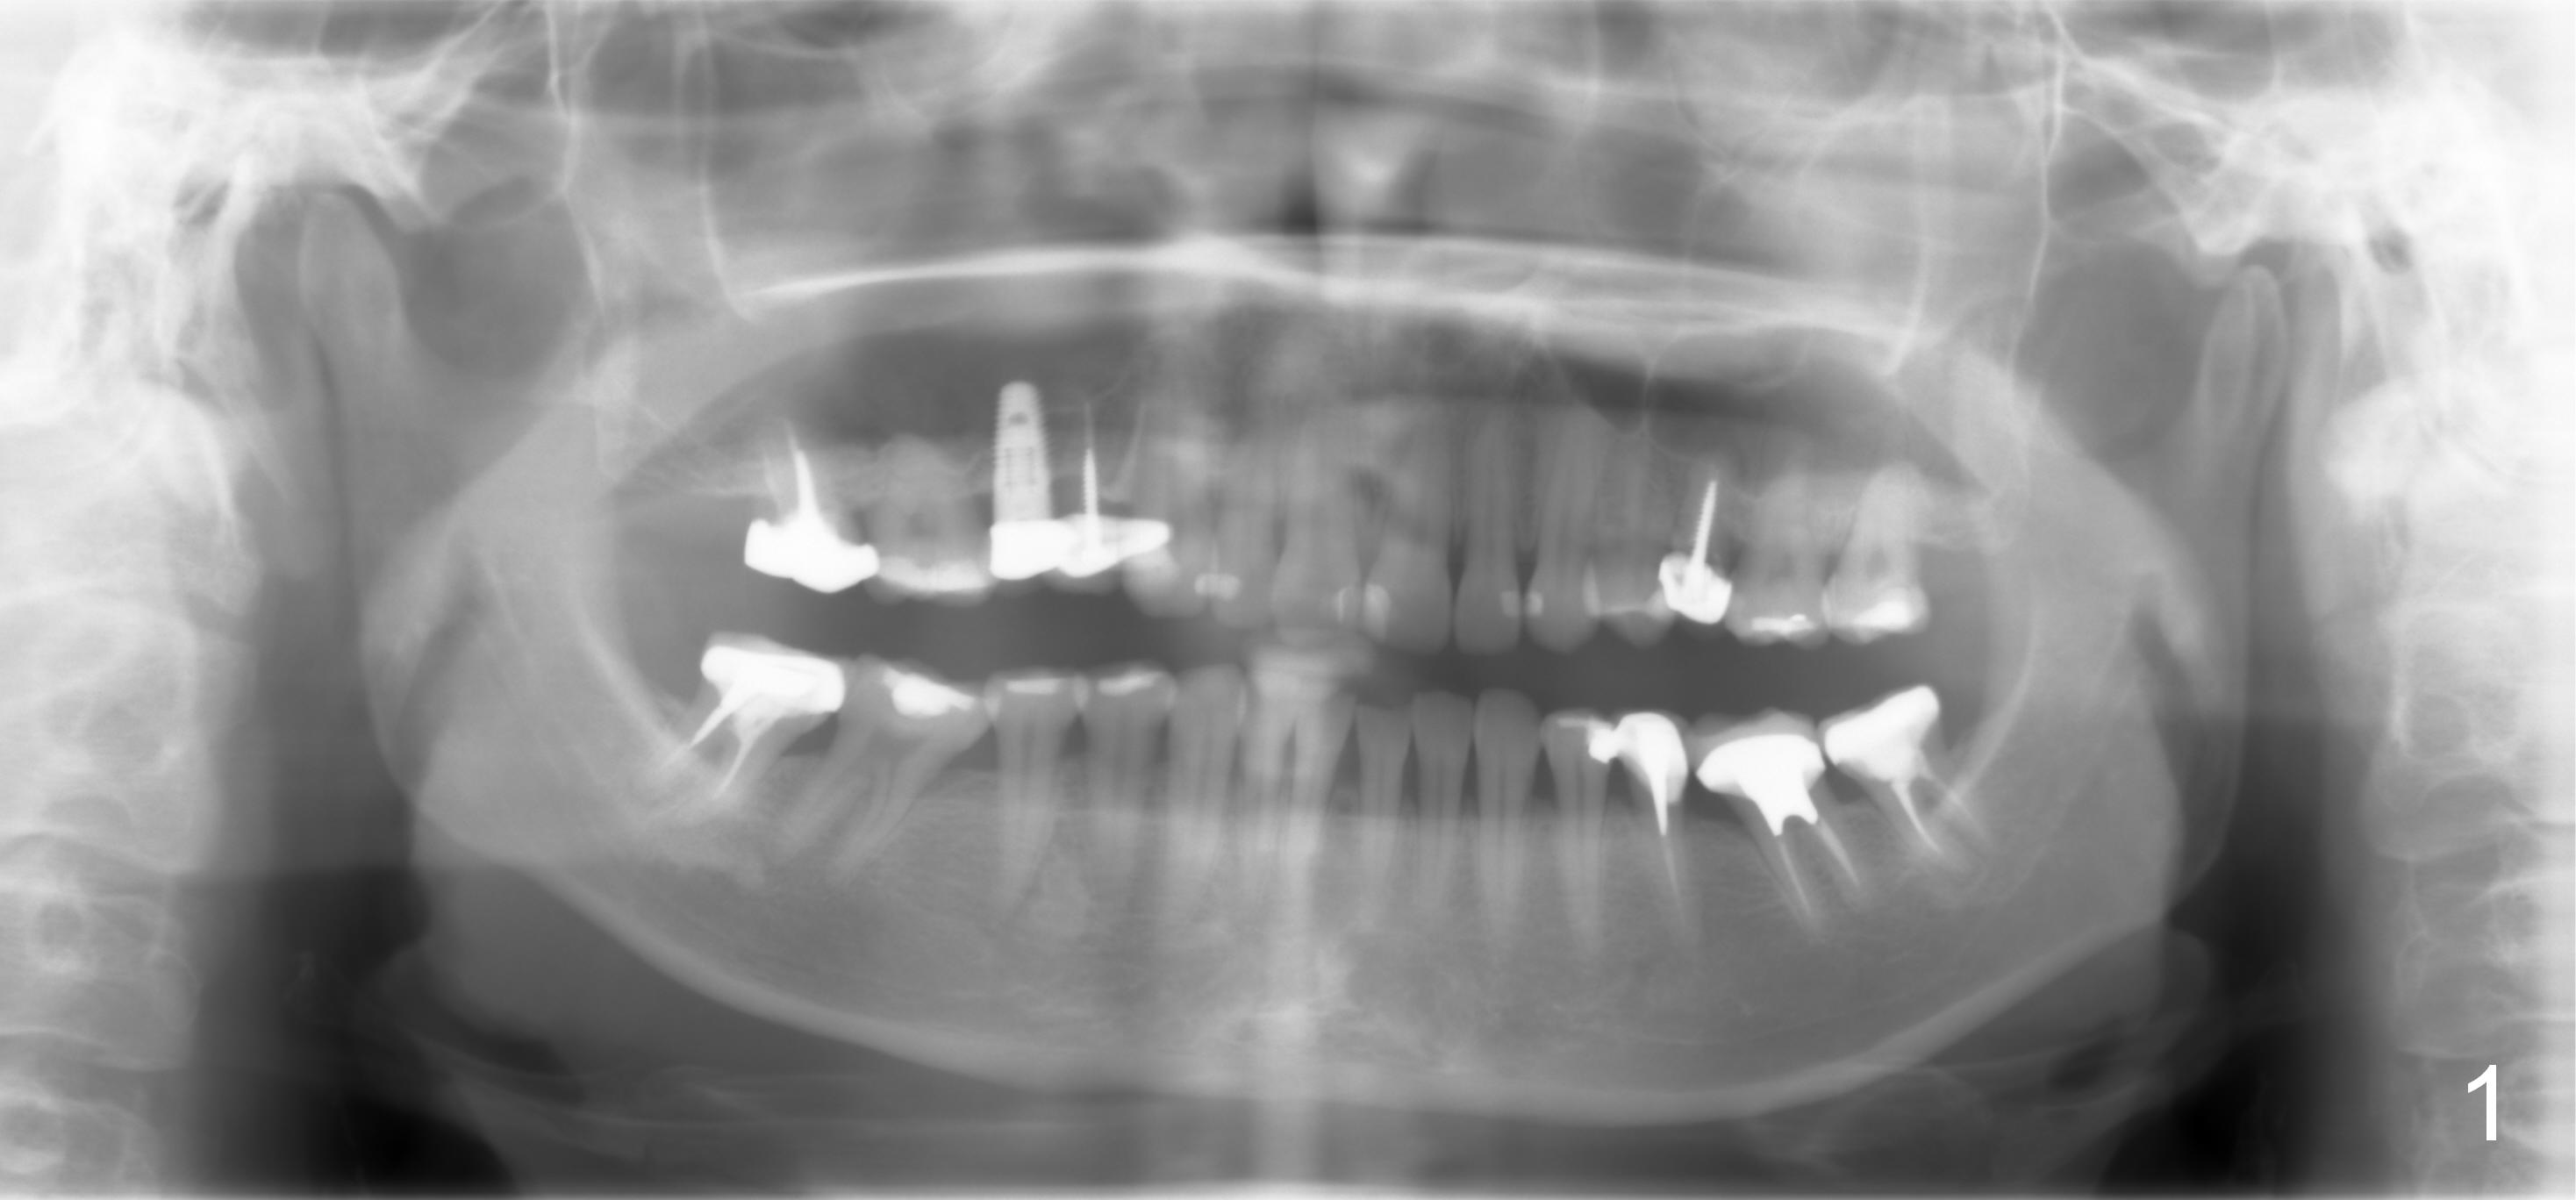

A 40-year-old lady has multiple restorations (Fig.1). The crown has dislodged from the tooth #13 twice in the last 2 years (Fig.2). When the tooth is extracted, a 4.5x10 mm bone level or 4.5x14 mm tissue level implant will be placed immediately with sinus lift (Fig.3).